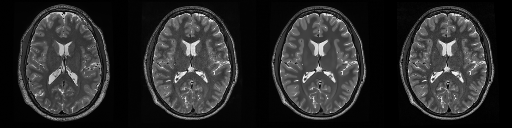

HCP T2w dataset

We utilize images from the publicly available Human Connectome Project (HCP) [51] T2-weighted (T2w) images dataset for the task of compressed sensing, which contains brain images from 47 patients. The HCP dataset includes cross-sectional images of the brain taken at different levels and angles.

Compressed sensing

We train a flow-based model from scratch on 10,000 randomly sampled images, utilizing the ncsnpp architecture [9] with minor adaptations for grayscale images. We employ compression rates , meaning . The measurement operator is given by a subsampled Fourier matrix, whose sign patterns are randomly selected. We evaluate our reconstruction algorithm’s performance on 200 randomly sampled test images.

We present the quantitative and qualitative results of compressed sensing in Tab. 1 and Fig. 4, respectively. As shown in Tab. 1, our method consistently achieves the best performance across varying compression rates . In Fig. 4, our method produces reconstructions that are more faithful to the original images, with fewer artifacts, leading to higher accuracy and clearer details.